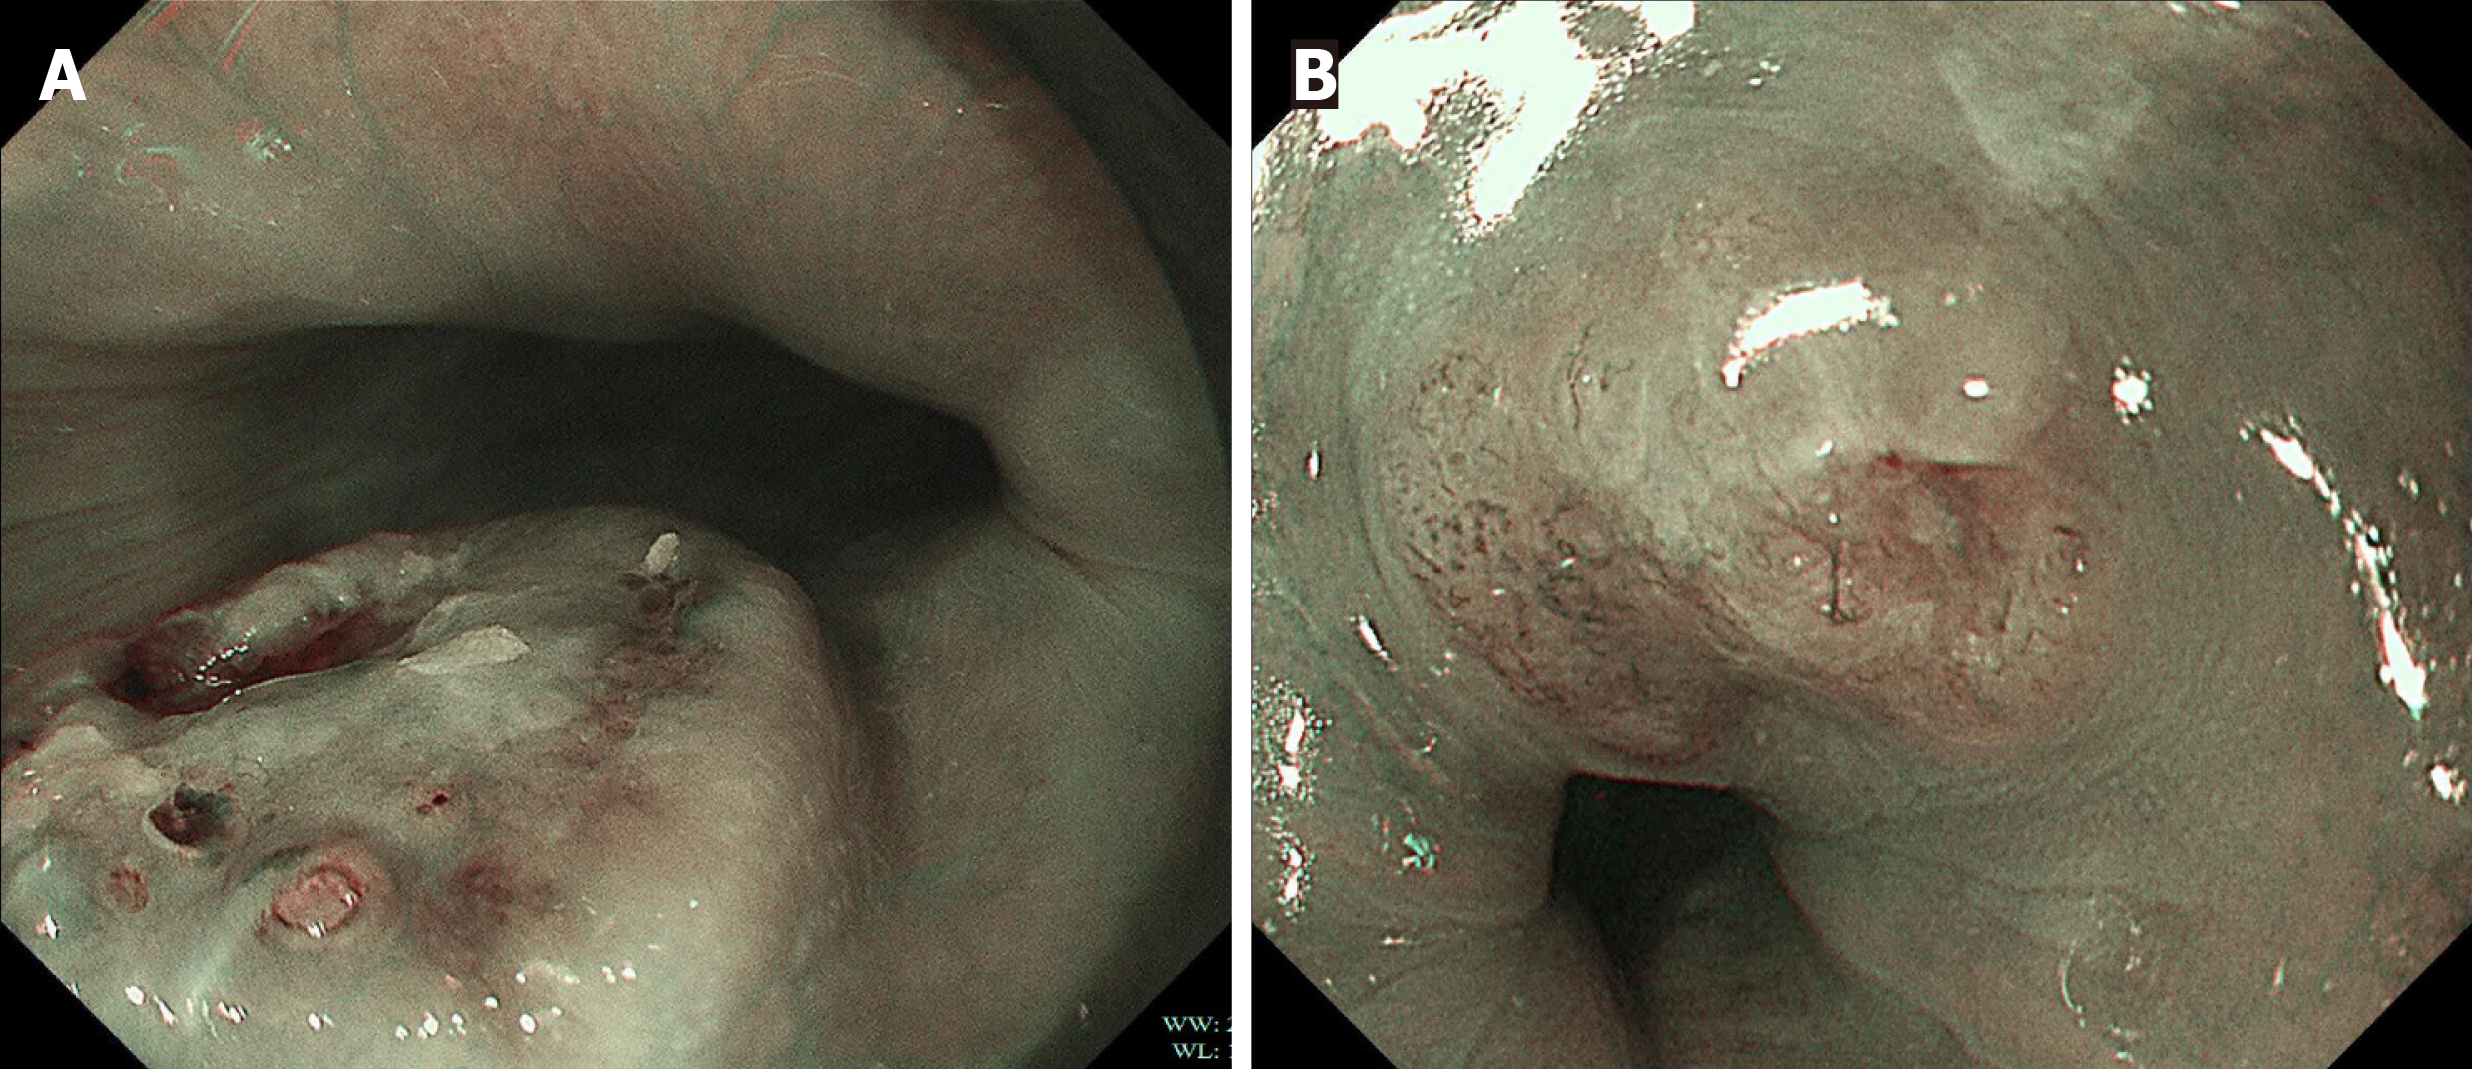

Under WLE, three of the four patients with early E-NEC exhibited localized mild ulceration on the lesion surface, while one presented with a smooth-surfaced polypoid lesion (Figure 1). The lesions were located at 27 cm, 28 cm, 30 cm, and 30 cm from the incisors and involved the mid to lower esophagus. The lesion sizes were between 0.5 cm × 0.6 cm and 1.2 cm × 1.1 cm. NBI was performed in two patients (Figure 2), which revealed irregular or dilated abnormal mic

Additionally, early E-NEC typically exhibits a dense and irregular microvascular network with twisted and dilated vessels, which appears under NBI as prominent brownish or tan vascular patterns in contrast to the adjacent normal tissue[24]. In contrast, esophageal leiomyomas generally show lower vascular density and more regular vascular stru